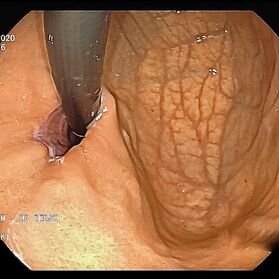

Mit einer Gastroskopie werden Speiseröhre, Magen und Zwölfingerdarm (der oberste Teil des Dünndarms) untersucht. Dazu wird ein geschmeidig biegsames, schlankes Endoskop mit eingebauter Digitalkamera durch den Mund eingeführt. Minimalste Veränderungen können dabei gesehen werden, die im Röntgenbild oder einer Kernspintomographie (MRT) noch gar nicht erkannt werden. Im Vergleich zu anderen bildgebenden Untersuchungsverfahren ist bei der Endoskopie neben der wichtigen optischen Beurteilung auch die sofortige Möglichkeit gegeben, Gewebeproben aus auffälligen Bereichen zu entnehmen. Dazu wird eine kleine Spezialzange durch einen Kanal im Endoskop geschoben und die Probe ganz präzise aus dem entsprechenden Gewebe gewonnen. Da die Schleimhäute schmerzunempfindlich sind, spüren Sie davon nichts. Die Proben werden von Spezialisten mikroskopisch untersucht und ermöglichen dann eine zielgerichtete Therapie; zum Beispiel wenn eine Magenschleimhautentzündung durch eine chronische Infektion ausgelöst wird, die mit einer Antibiotikakur erfolgreich behandelt werden kann.